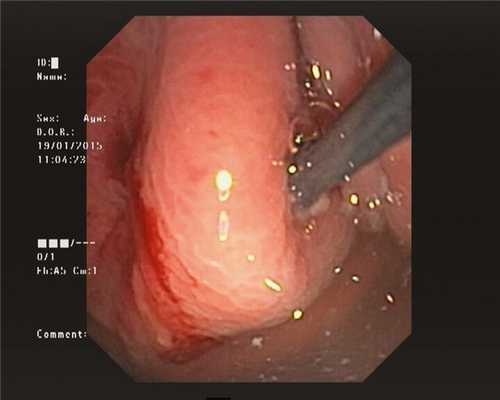

3. Электрокоагуляция тканей желудка и стенки кисты с последующей цистотомией стенки кисты посредством 8,5 Ch цистотома (MTWEndoscopieManufaktur, Germany) (рис. 2). Рис. 2. Цистотомия стенки кисты устройством МТW (MTW Endoscopie Manufaktur, Германия) (случай 1).